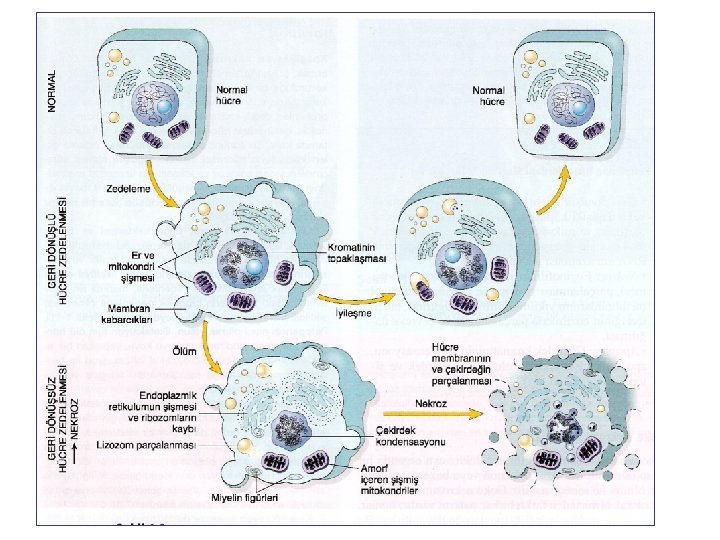

Normal hücre Hücre hasar etkeni Hücresel adaptasyon İrreversibl hücre hasarı Reversibl hücre hasarı Hücre ölümü Nekroz Apopitoz

• Hücre Zedelenmesi: 1. Geri Dönüşlü (Reversibl) 2. Geri Dönüşsüz (İrreversibl) Temel olay: Membran Hasarı • Önce fonksiyon kaybı, sonra morfolojik değişiklikler İskemi durumunda kalp kası hücreleri 1 -2 dk içinde kasılamaz hale gelir, 20 -30 dk sonra ölüm olur.

Zedelenmede morfolojik değişiklikler • Reversibl (geri dönüşlü) hasar - hücresel şişme - yağlanma (yağ metabolizmasında rol oynayan hücrelerde- karaciğer, kalp) mikroveziküler makroveziküler

Reversibl (geri dönüşlü) hasar • Hücre şişmesi (plazma membranındaki ATP bağımlı iyon pompası bozulur. ) • Mitokondri ve ER başta olmak üzere organeller şişer. • Ribozomlar granüllü ER’dan ayrılır- protein sentezi bozulur. • Plazma memb. da kabarcıklar ortaya çıkar. • Oksidatif fosforilasyonda azalma (mitokondride ATP sentezinin bozulması) → Anaerobik glikolizde artma • Laktik asit artışı • p. H düşmesi • Çekirdek kromatininde topaklaşma

İskemik ve hipoksik hücre hasarı: İrreversibl (geri dönüşsüz) hasar: (Geçiş noktası ? ) • Kritik olay: 1. Geri dönüşümsüz mitokondri hasar 2. Plazma ve organel membranlarında bozulma • Lizozom parçalanması – Sindirim enzimleri açığa çıkarorganeller parçalanır. • Nükleer büzüşme, parçalanma, erime • Myelin figürler: Hücre membranından oluşan büyük fosfolipid kitleleri

Hücre Ölümü NEKROZ: Her zaman patolojik Membran zedelenmesi şiddetli ØLizozom membran bütünlüğü bozulur ve enzimler sitoplazmaya geçer. Organeller sindirilir. ØPlazma membran bütünlüğü bozulur. Hücre içeriği dışarı çıkar ve çevrede inflamasyon yanıtı oluşur. Ana hücre ölüm yolu APOPTOZ: Çoğunlukla fizyolojik (görevini tamamlamış veya zararlı olabilecek hücrelerin ortadan kaldırılması, dokudaki hücre sayısının sabit tutulmaya çalışılması) nadiren patolojik (DNA zedelenmesi) Programlı hücre ölümü (sıkı kontrol, aktif enerji) Membran bütünlüğü tam olarak bozulmaz. İnflamatuar reaksiyon gelişmez.